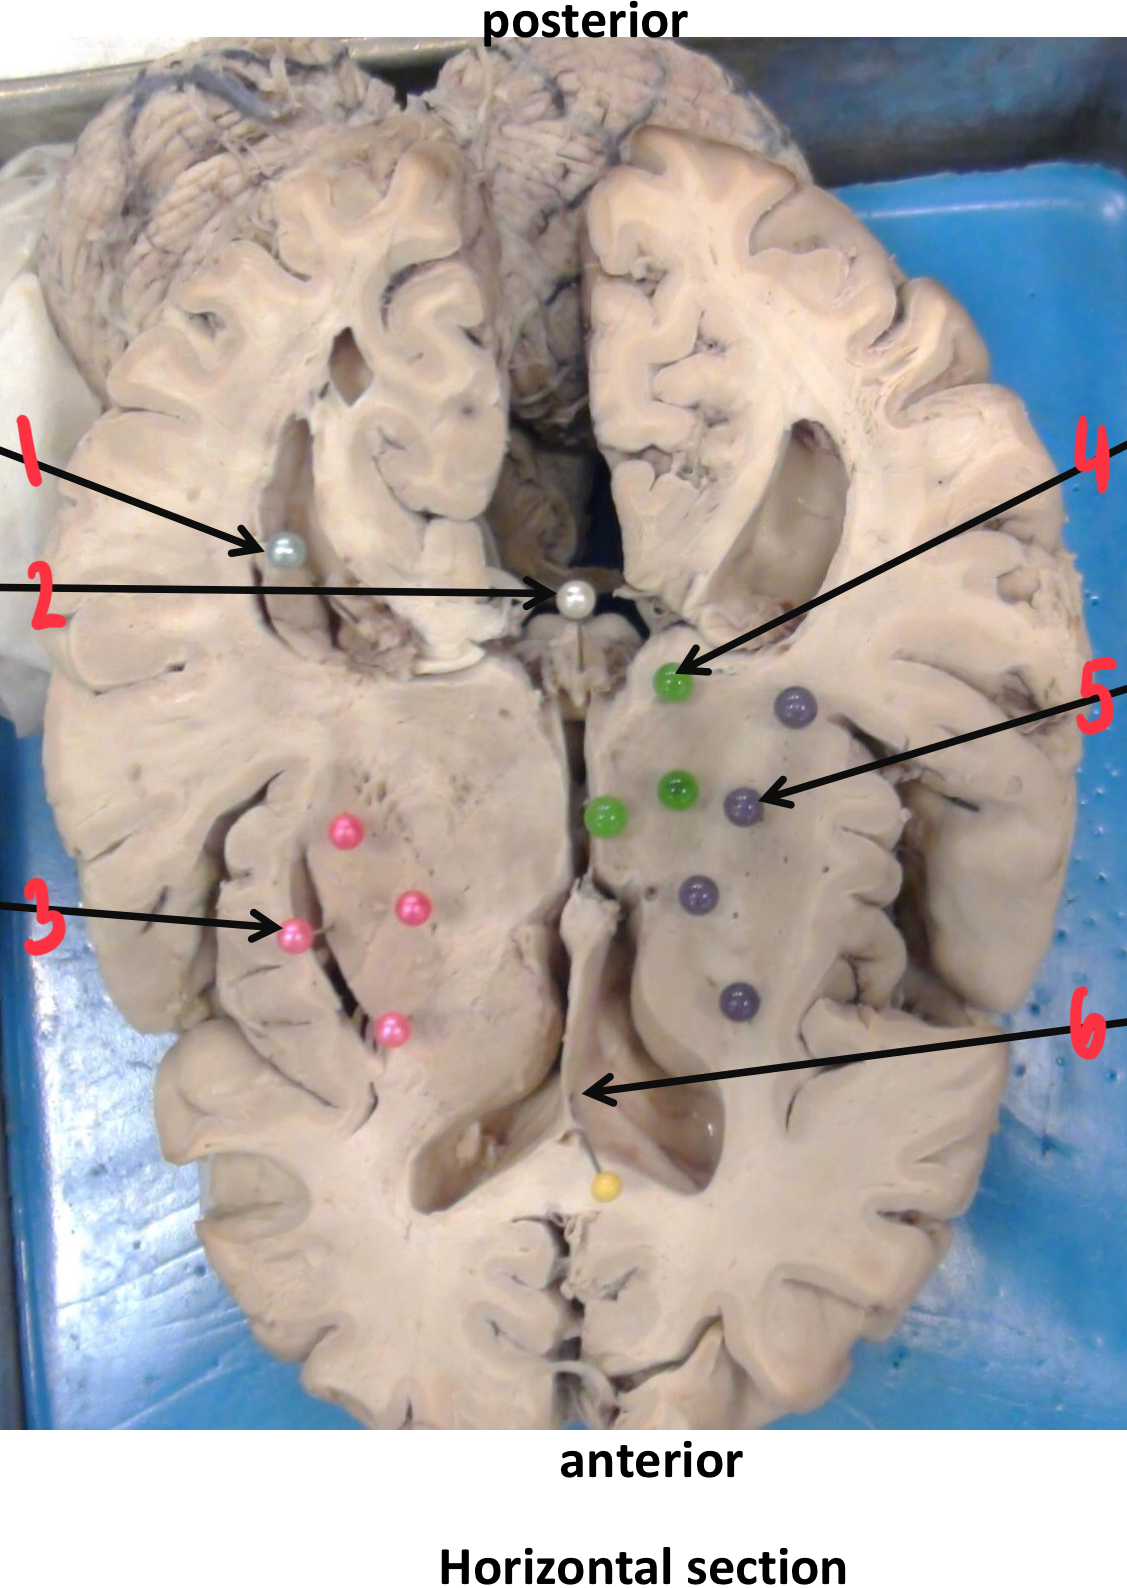

1

corpus callosum

2

caudate nucleus

3

insula (island of Reil)

4

mamillary body